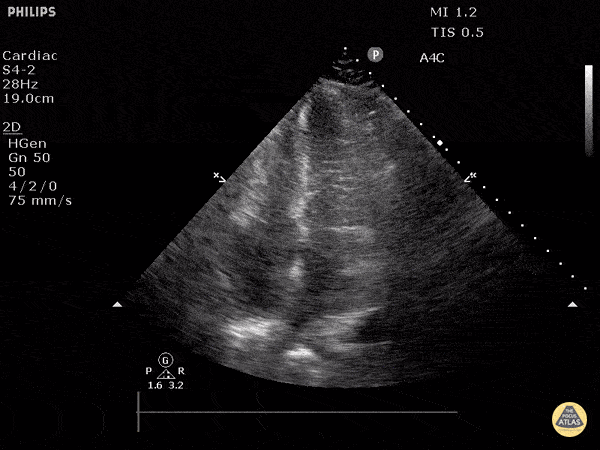

Left Ventricular Dysfunction - Hyperdynamic State